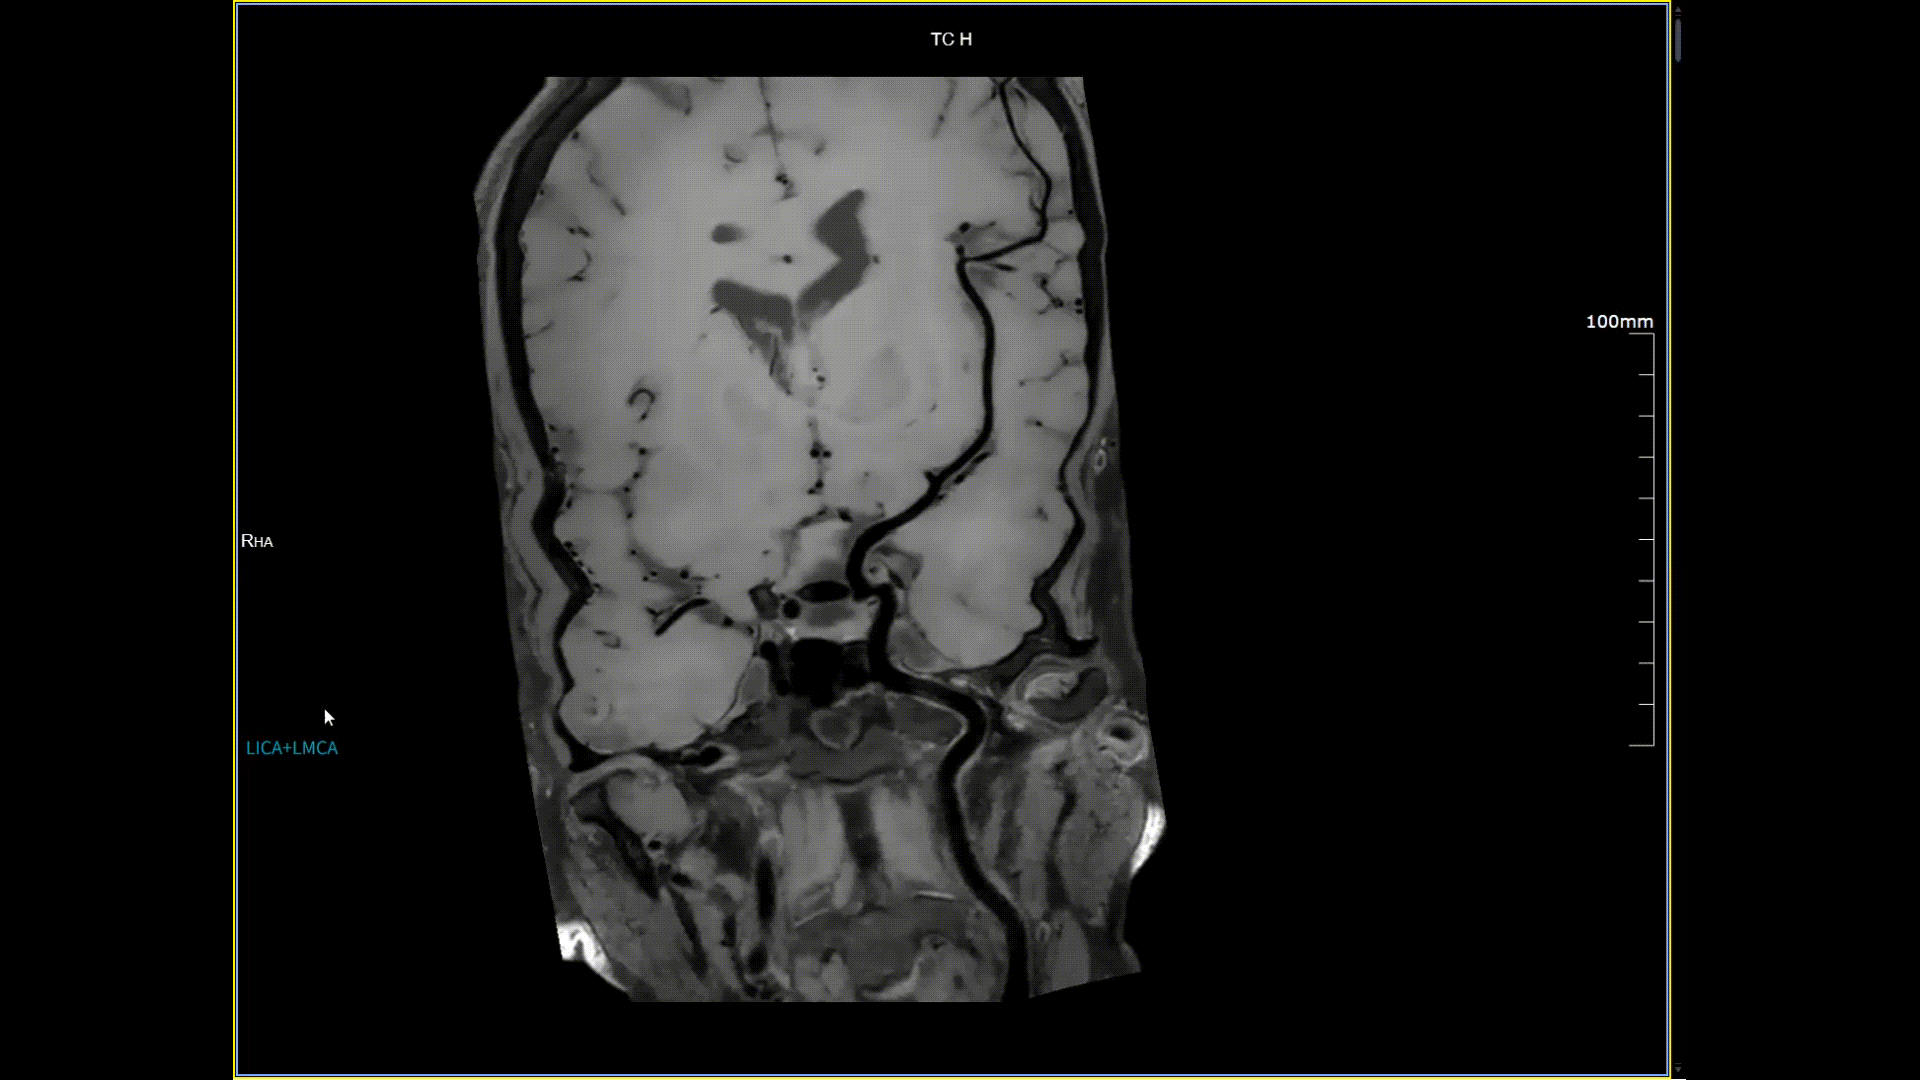

接受了河北省首台5.0T超高场核磁共振头颅血管成像检查,图像清晰精准地反映出患者右侧小脑区域的血管畸形情况,该患者对果冻传媒

的诊疗实力与服务温度给予充分肯定。相较于传统核磁共振,这台设备实现了“超高场全身各部位成像”的技术突破,它以业界领先的超高性能实现亚毫米级超高清成像,尤其在神经、心血管、体腹、关节等部位肿瘤疾病的早期发现、精准评估、个性化治疗方案制定中提供了的强大影像支持,将为全省乃至周边地区患者带来更优质、更精准的医疗服务。

5.0T磁场强度远高于其他设备,使得氢原子核在磁场中的响应信号极大地增强。这就像在安静的房间里能听清细微的声音一样,高信噪比能让医生看到更微小、更模糊的病变结构。例如上述患者的检查,该设备可以呈现0.2x0.2毫米高分辨率的图像以及动态显示血管走行,使得病变血管的细微解剖结构、分布及其与周边脑组织的关系得以直观呈现,为临床医生进行精准诊断并制定后续治疗方案提供了重要的影像学依据。

4D非造影剂头颅血管成像